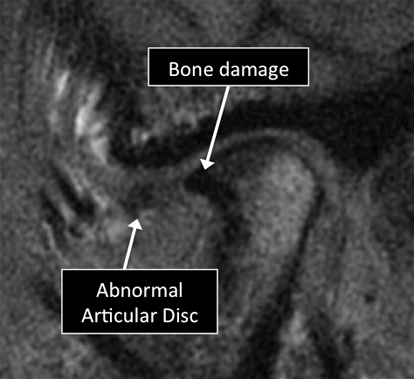

MRI can visualize many of the different structures in the TMJ. Certain diseases affecting those structures can be diagnosed using MRI. Common diseases include abnormal position, tears and degeneration of the articular disc, osteoarthritis, tumors, among others.

MRI examinations showing normal (top) and abnormal (bottom) TMJ.

Why Translational MRI of the TMJ?

In the TMJ, as in many other parts of the body there is certain structures that can’t be seen with the standard MRI used in the clinical practice. There are new techniques that allow the visualization of some of the structures which are otherwise “invisible” in the standard MRI. Some of these “invisible” structures are unique to the TMJ (articular disc) and other are found in other parts of the body (e.g. tendons, ligaments, cortical bone).

TMJ MRI examinations using the standard MRI techniques (top) and translational MRI techniques (bottom).